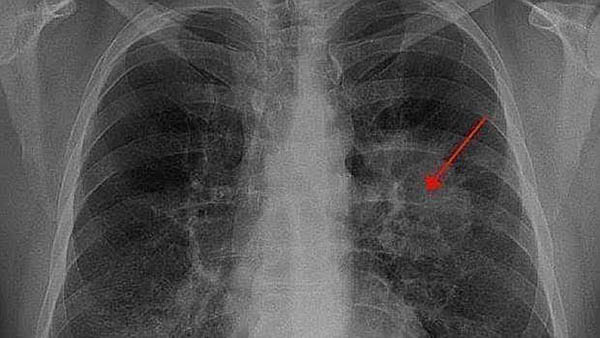

Radiografía de un paciente con cáncer de pulmón - Archivo

Beijing, 16/08/2018 (Pueblo en Línea) – Investigadores chinos del Instituto de Zoología de la Academia de Ciencias china han descubierto 21 proteínas clave que pueden inhibir o estimular el crecimiento de células de cáncer de pulmón, según un estudio publicado en la revista internacional Cancer Letters, noticia de la que se hace eco el diario ABC.

Mediante técnicas de cribado genómicas, los investigadores probaron 1.530 factores de transcripción (FT), y descubrieron que once de ellos eran supresores tumorales que impedían el crecimiento de células cancerígenas, mientras que otros diez tenían el potencial de causarlo.

Los factores de transcripción son proteínas clave ligadas a la secuencia de ADN que controlan la expresión génica y decodifican la información en el genoma humano.

El cáncer de pulmón representa el 20% de todas las muertes por cáncer en el mundo y la amplia mayoría del 80-90% son causadas por el tabaquismo, según la Agencia Internacional de Investigación sobre el Cáncer (IARC).